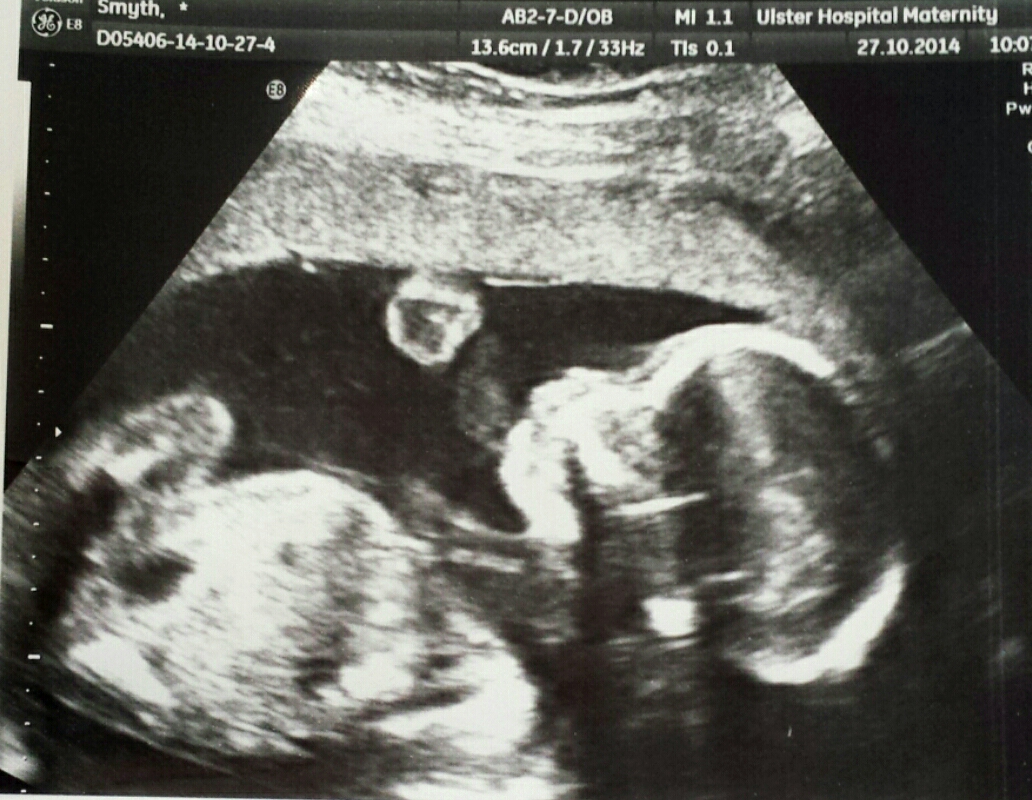

This is my 20 week scan. Can you tell if it's a boy or a girl? Use any theory :)Attachment 22127

I'd guess boy off of the heap shape :)

I have a feeling it's a boy! Any other guesses anyone?!